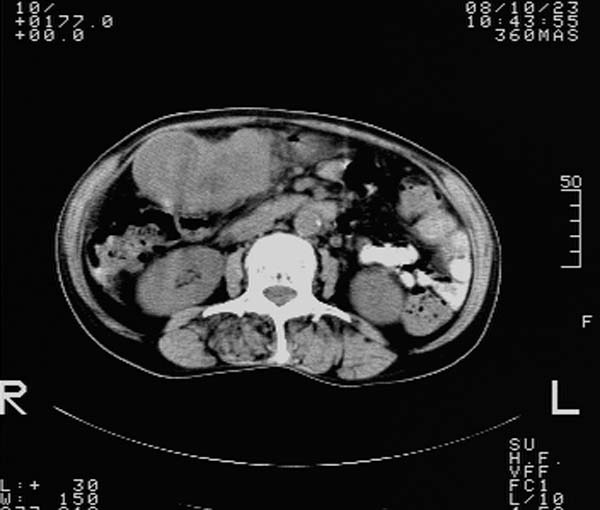

f,67y。反复右上腹痛。余无异常。

前五幅未服造影剂。后面图像有上传重复的。请战友们发表意见。

胆囊结石、胆囊癌伴邻近脏器受侵,不除外黄色肉芽肿性胆囊炎,建议增强扫描。肝多发囊性占位性病变,囊肿或囊性转移。

胆囊内结石,胆囊壁不规则增厚,胆囊胃窦区解剖结构欠清晰,楼主提示为少见病,考虑bouveret综合征?黄色肉芽肿性胆囊炎?肝内多发低密度占位,建议增强或b超